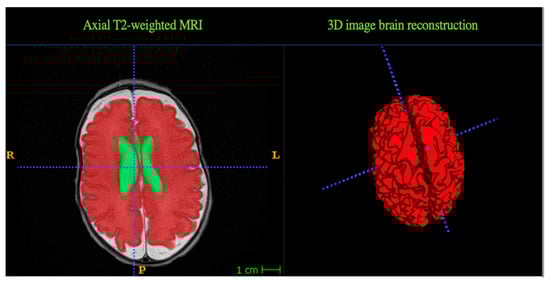

2.3. MRI Data Acquisition